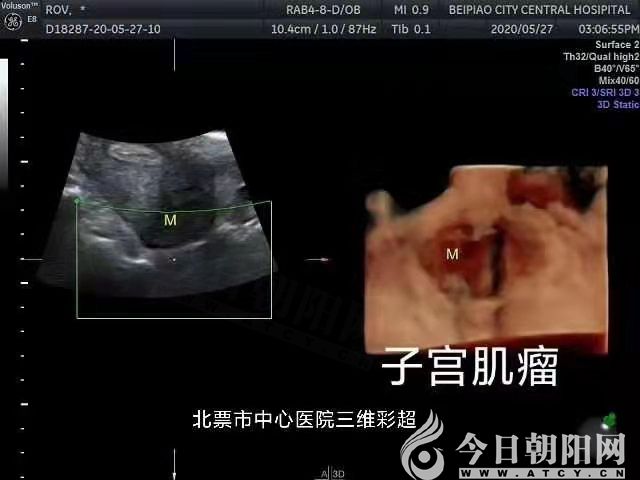

好消息!北票市中心醫(yī)院開(kāi)展多項(xiàng)三維超聲檢查項(xiàng)目

近日,遼寧省北票市中心醫(yī)院超聲醫(yī)學(xué)科陸續(xù)開(kāi)展了婦產(chǎn)、乳腺、甲狀腺等淺表器官及腹部、泌尿,腔內(nèi)等三維超聲檢查項(xiàng)目(咨詢(xún)電話(huà):5080482),極大地滿(mǎn)足了城鄉(xiāng)廣大患者的就診需求,同時(shí)保證了臨床診療工作的順利有序進(jìn)行,提高了工作質(zhì)量和效率。

婦產(chǎn):子宮、附件、胎兒及其附屬物及腔內(nèi)超聲等;